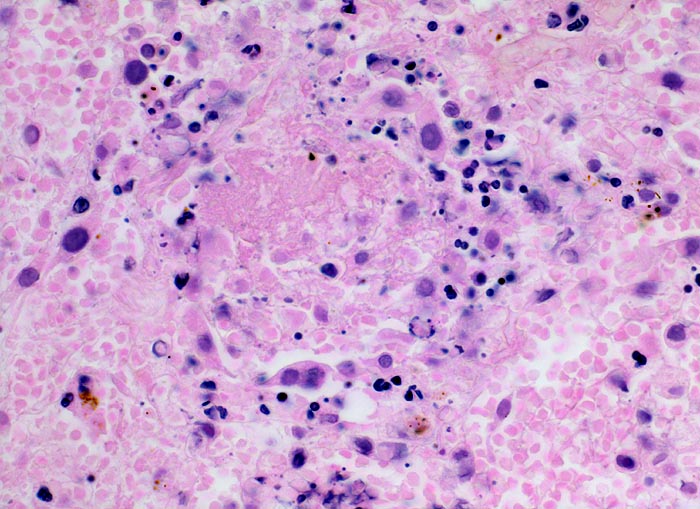

Morphologische Merkmale:

- Scharf begrenzte dreiecksförmige hämorrhagische Nekrose des Lungenparenchyms.

- Alveolen gefüllt mit zerfallenden Erythrozyten, Kerntrümmern und Fibrin.

- Lungengerüst erhalten im Randbereich der Nekrose, nicht mehr erkennbar im Zentrum.

- Abgeblasste Zellkerne in der Nekrosezone.